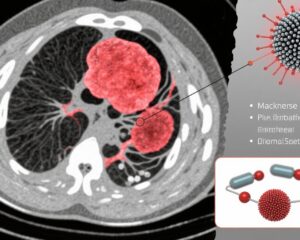

This study introduces a novel nanoplatform, LT@MnO@MON-HA (LMMH), engineered for tumor microenvironment responsiveness enabling controlled release of manganese ions (Mn2+) and the mitochondrial glycolysis inhibitor lonidamine (LT). The methodology involves:

– Synthesis of manganese oxide (MnO) nanoparticles encapsulated within an organic mesoporous silica (MON) shell containing disulfide bonds enabling glutathione (GSH)-responsive degradation.

– Encapsulation of mitochondria-targeted lonidamine (LT) within mesopores, followed by surface coating with hyaluronic acid (HA) for tumor-specific targeting via CD44 receptor affinity.